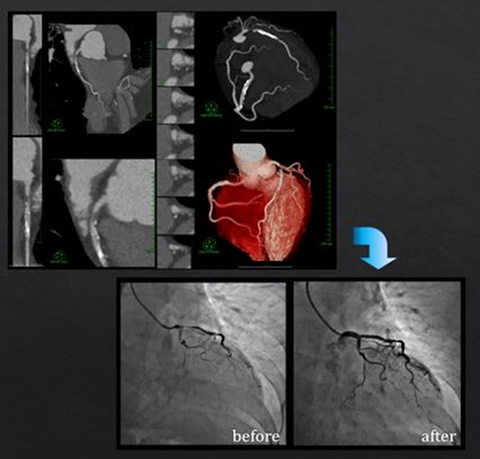

以下に経験した一例を示す。

70歳台女性

1週間前に駅歩行中胸部圧迫感。

近医受診の後、精査の為当院循環器内科へ紹介となった。

HT(+) DM (+) HL(-)  家族歴:なし

CCT:LAD#6に高度狭窄疑い

即日CAG(PCI stand by)へ

CAG:CCTと一致する部位(#6 just)に75%~90%狭窄を認めた為、即時PCIに移行

PCIにて十分な拡張が得られたことを確認した後経過観察入院

翌日退院となった

201704_voice_img_ct_02_08.jpg

図7. CCTで有意狭窄を認め即日PCIとなった症例

これは前述の恩恵があってはじめて実現できたものであるが、これにより診察から結果説明までの一連の流れがスムーズになり患者様の時間的な負担は大きく軽減した。また緊急を要する治療が必要になった際も、日勤帯で稼動しているカテーテル検査室へそのまま移動できるため病院として特別な体制をとる必要もなくなった。